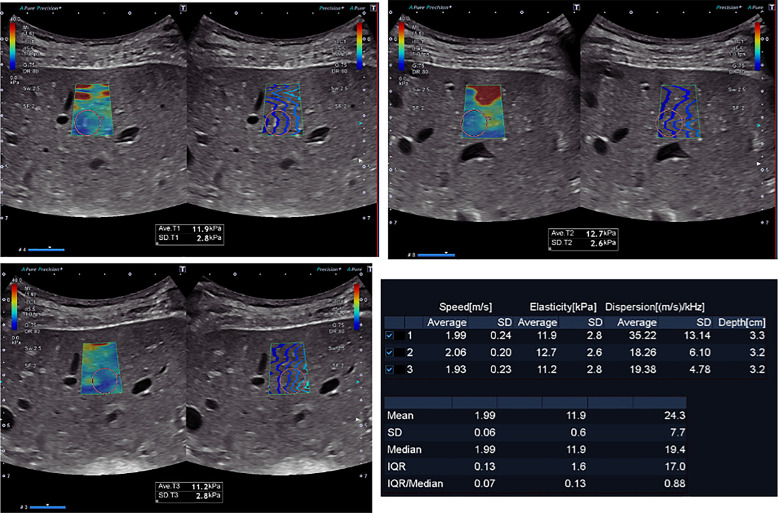

Case presentation: We present a case of hepatic fibrosis with splenomegaly and severe pancytopenia as a tardive complication after bilateral nephrectomy in 47-year-old ADPKD patient.

Conclusion: This finding underscores the critical significance of meticulously examining the anatomical relationship between polycystic kidneys and the liver before performing nephrectomy. Additionally, it highlights the importance of assessing liver involvement and associated complications. By integrating liver assessment into the criteria, we can significantly enhance patient care and improve the overall management of ADPKD before kidney transplantation.